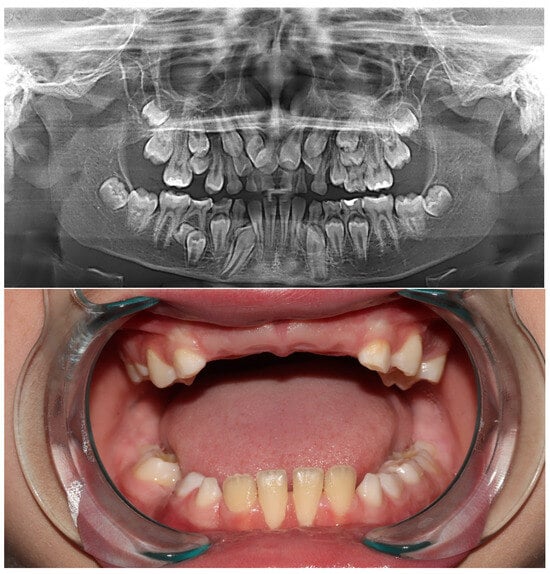

The patient was admitted to the Dental Clinic of the Faculty of Medical Sciences, University of Kragujevac due to unerupting teeth in the frontal region. His parents reported an unremarkable medical history. During the general physical examination of the hands and the phenomenon of shoulders close to the front of the body, it did not indicate that it was Cleidocranial Dysplasia (CCD). However, a molecular genetic analysis was proposed to exclude a diagnosis of CCD. Considering the patient’s age (eleven years), a retroalveolar X-ray was initially performed, followed by a panoramic X-ray. After a thorough examination of the panoramic X-ray, primary teeth were extracted in the frontal region, and it was decided that a CBCT scan would be performed to obtain more data regarding the supernumerary teeth.

Figure 1.